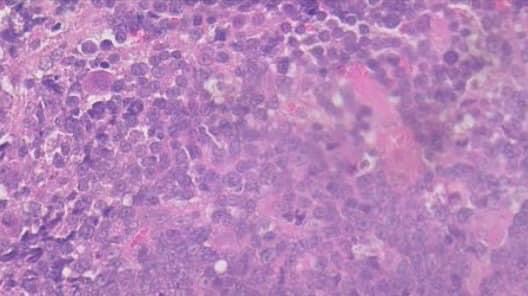

病理切片診斷結果為貓淋巴瘤,可惜後續小花二次貧血且伴隨急性腎衰竭,最後主人決定帶回家安寧。